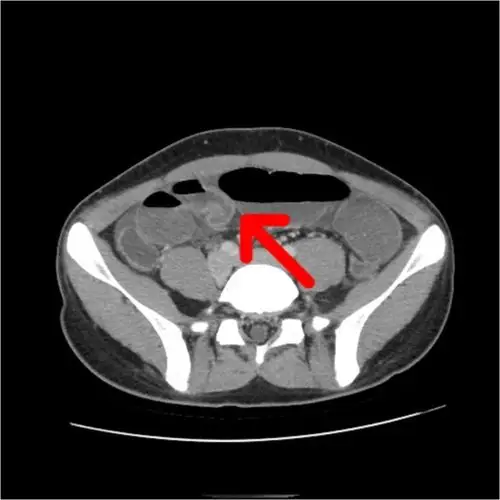

小肠憩室一例 - 普通外科讨论版 -丁香园论坛

小肠憩室图片 - 普外科讨论版 - 爱爱医医学论坛

【病例讨论】(小肠憩室)已经手术证实,大家一起来学习吧 - 普通外科讨